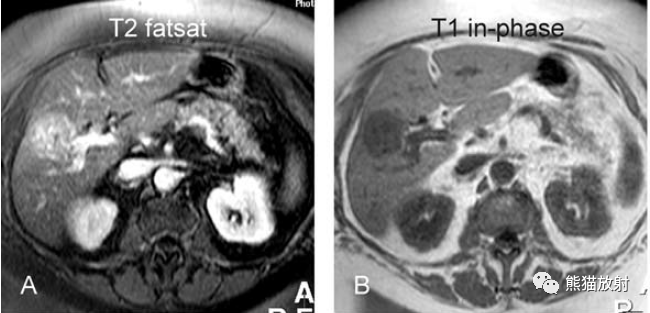

T2壓脂(T2 fatsat):膽囊窩內(nèi)膽囊癌病變較肝臟為高信號,病變頂部向肝內(nèi)擴(kuò)展;

T1同相位(T1 in-phase):膽囊癌病變較肝臟為低信號;

膽囊癌。A~D圖:上方層面,表現(xiàn)如上所述,形成腫物侵及肝臟。E、F圖:下方層面示膽囊壁不規(guī)則增厚,明顯不均質(zhì)強(qiáng)化。